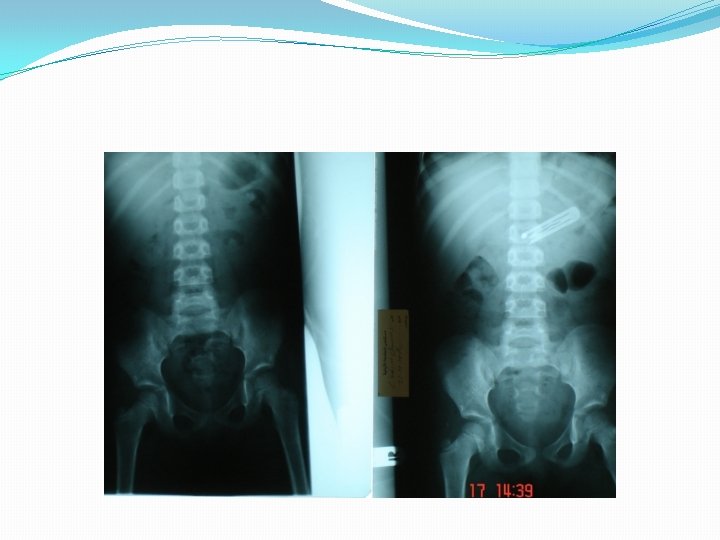

Radiographic examination �consists of anteroposterior and lateral views of the extended neck and chest. � 56% of patients will have a normal chest radiograph �CXR findings: �air trapping : the most common sign �atelectasis �mediastinal shift �Pneumonia �a radiopaque object

Air trapping